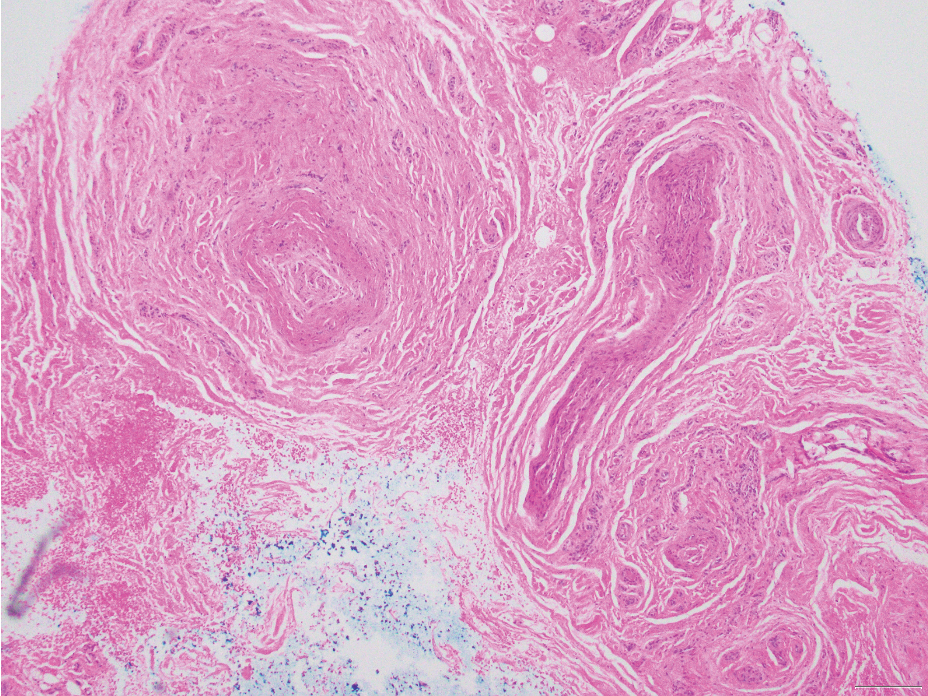

Neurofibromas are nonencapsulated lesions composed of spindle cells with wavy nuclei dispersed in a myxoid background.8 Neurofibromas can manifest in various locations throughout the body, including the skin, subcutaneous tissues, and internal organs. They are slow-growing tumors but may accelerate during periods of hormonal changes, such as pregnancy and puberty, or in cases of malignant transformation.8 Although plexiform neurofibromas are benign, malignant transformation can occur, particularly in patients with neurofibromatosis type 1 (NF1).8,9 Neurofibromas may assume one of 3 growth patterns: localized, diffuse, or plexiform.8 Plexiform neurofibromas exhibit a multinodular, ropelike growth pattern with a mix of Schwann cells and fibroblasts (Figure 2).8,9 These lesions are pathognomonic for NF1 and can infiltrate the surrounding tissue. They may involve large nerve trunks, leading to a more complex growth pattern compared to solitary neurofibromas.8,9 The plexiform variants of both neurofibromas and PEN demonstrate a multinodular growth pattern; however, plexiform neurofibromas are nonencapsulated and show a more diffuse infiltrative nature, whereas plexiform PEN remains well circumscribed. Additionally, plexiform neurofibromas are associated with NF1, while plexiform PEN lacks this genetic association.

FIGURE 2. Plexiform neurofibromas exhibit a multinodular, ropelike growth pattern, involving a mixture of Schwann cells and fibroblasts with background features consistent with more typical neurofibroma (H&E, original magnification ×20).